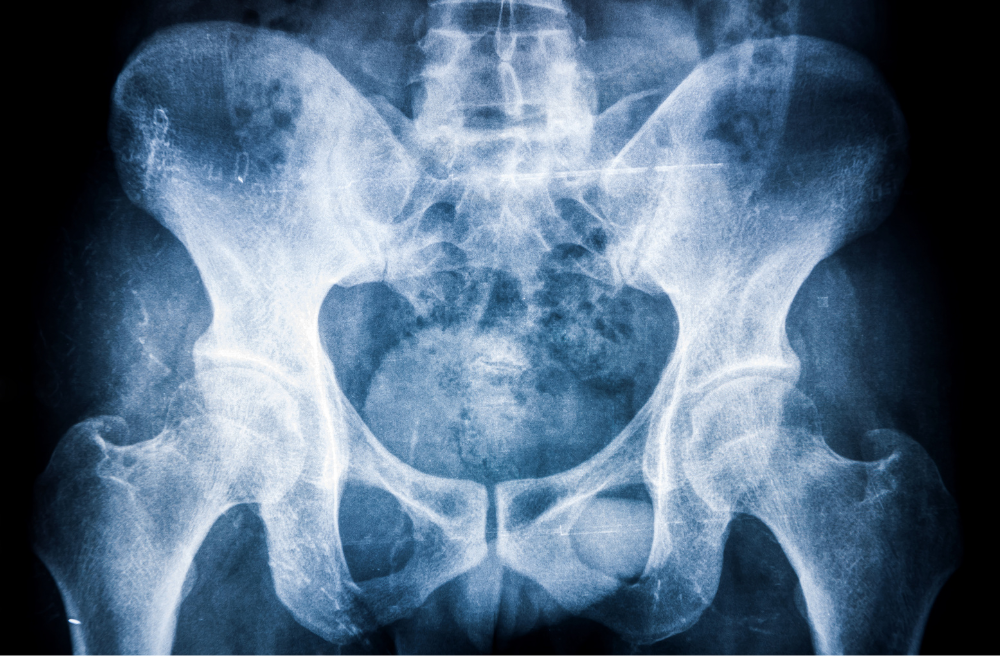

강직성 척추염은 주로 척추, 특히 꼬리뼈 부위의 천장 관절 쪽에 영향을 미치는 만성 관절염의 일종이지만 경우에 따라 다른 관절에도 영향을 미치곤 합니다.

'강직성 척추염'은 명칭 그대로 허리 부위에 염증이 생겨 움직임이 둔해지는 병이라고 생각하시면 됩니다. 하지만 척추의 유연성과 가동 범위에 제한이 걸리면서 어깨, 무릎, 발목 등의 다른 관절에도 통증을 일으키곤 하지요.

강직성 척추염은 자가 면역성 염증 장애에 해당하는데, 쉽게 말하자면 우리 몸의 면역 체계가 반대로 우리 몸을 공격한다는 것을 의미합니다. 강직성 척추염에 의한 면역 체계 이상은 척추의 관절과 인대를 공격하여 염증과 손상을 일으키게 됩니다.